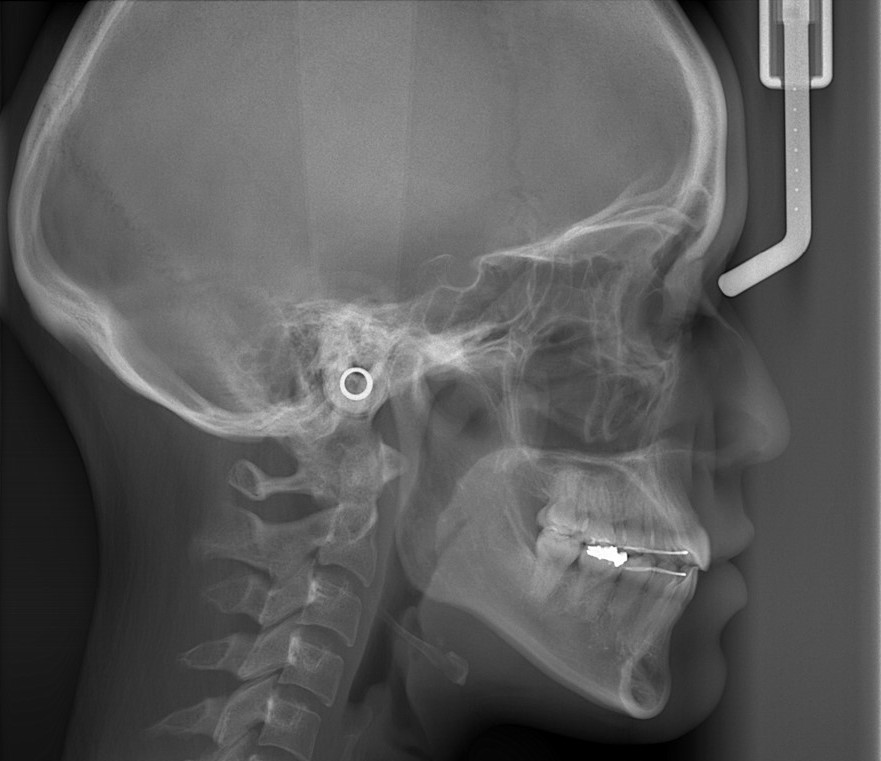

レントゲン写真でも比較してみましょう

左側が矯正治療前、右側が矯正治療後